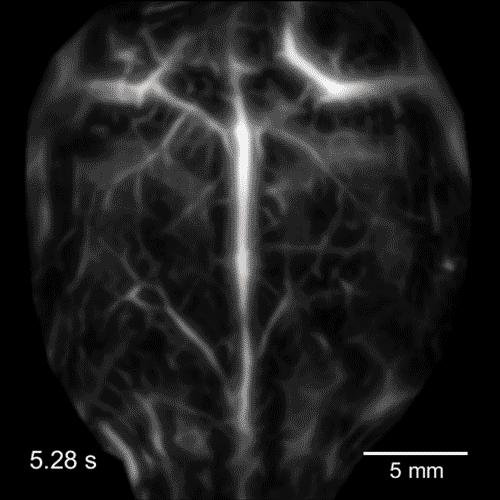

The technique dubbed "single-impulse photoacoustic computed tomography (SIP-PACT)" uses the best of both light and ultrasound to peer inside living animals. Researchers at Duke University and CalTech have shown this hybrid imaging technology breaks the longstanding resolution and speed barriers in small-animal whole-body imaging. It provides a full cross-sectional view of a small animal's internal functions in real time.

In the new paper, Yao and colleagues led by Dr. Lihong Wang at the California Institute of Technology add the highly desired speed and panoramic views to the imaging technology's repertoire. They have built a circular ultrasonic detector and a fast data-acquisition system that can triangulate the origin of an ultrasonic wave from anywhere within the body of a small animal. And with the help of a fast laser that operates within the safety limit, the upgraded device can image the full cross-section of an adult rat 50 times per second, providing detailed movies of its inner workings with 120-micrometer resolution.

"The panoramic effect provides information from all directions and all angles, so you do not lose any information from each laser shot," said Yao. "You can see the dynamics of the body in action -- the pumping of the heart, the dilation of arteries, the functioning of various tissues."

In the paper, Yao and colleagues describe how they use these abilities to track cancerous melanoma cells traveling through blood vessels of a mouse. They also demonstrate the ability to watch entire neural networks firing in real time.